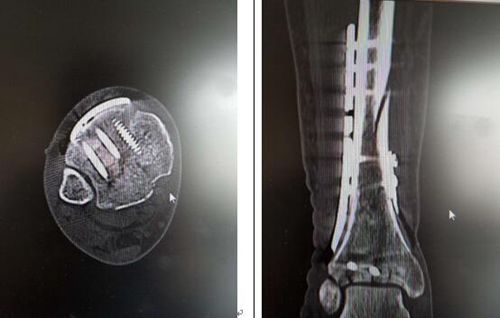

上海-仁慈專家同臺,聯(lián)手實(shí)施pilon骨折切開復(fù)位內(nèi)固定術(shù)

在行至Matteo病床時(shí),考慮到其病情較為嚴(yán)重。在與王旭主任溝通后,王旭主任決定與曹廣超主任團(tuán)隊(duì)一起為Matteo實(shí)施雙pilon骨折切開復(fù)位內(nèi)固定術(shù),手術(shù)順利完成。

曹廣超主任說,“這臺手術(shù)做得非常好。目前,患者傷口恢復(fù)良好。”經(jīng)過兩周的觀察,Matteo已于昨日出院回家。